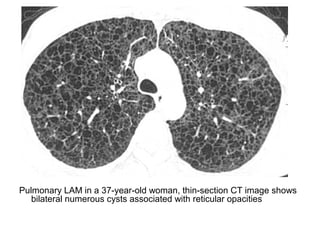

Pulmonary LAM in a 37-year-old woman, thin-section CT image shows

bilateral numerous cysts associated with reticular opacities